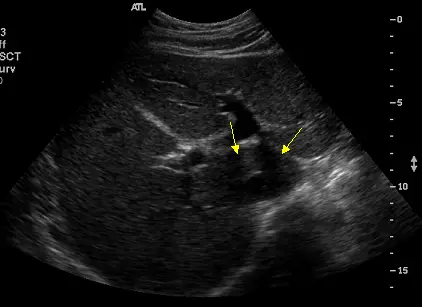

下圖為肝臟之橫切面,箭號所指為肝臟的那一個部位?

本題肝臟橫切面超音波影像中,兩個黃色箭頭指向肝臟中央偏後方的一個實質組織區塊,具體位置特徵如下:

- 位置:位於肝臟的後內側,在下腔靜脈(inferior vena cava, IVC)的前方,兩側由肝靜脈分隔

- 後方:緊鄰下腔靜脈(IVC)暗管狀結構

- 前/左側:靜脈韌帶裂(fissure for ligamentum venosum)

- 右側:IVC 右緣

- 回音特徵:與周圍肝實質相似的均質等回音,但在解剖位置上與其他肝葉明顯分隔

- 典型解剖標誌:箭頭所指位置位於 IVC 前方的「島狀」實質組織,此為尾葉(Couinaud segment I)的超音波辨識要點

此影像特徵明確對應肝臟尾葉的解剖位置。